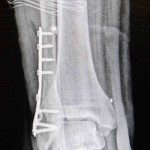

Ortopedi polikliniklerine en sık ayak bileği, diz ve omuz yaralanmalarıyla başvurulduğunu belirten Demirbaş, futbol nedeniyle yaralanma oranlarının da ilk sırada yer aldığını söyledi. Konuya ilişkin Demirbaş, “Futbolda menisküs yırtıkları, ön çapraz bağ yırtıkları, iç ve dış yan bağ yaralanmaları, aşil tendon kopmaları ve ayak bileği bağ yaralanmaları çok sık görülüyor. Ayrıca spora bağlı kırıklar da önemli bir yer tutuyor” ifadelerini kullandı.